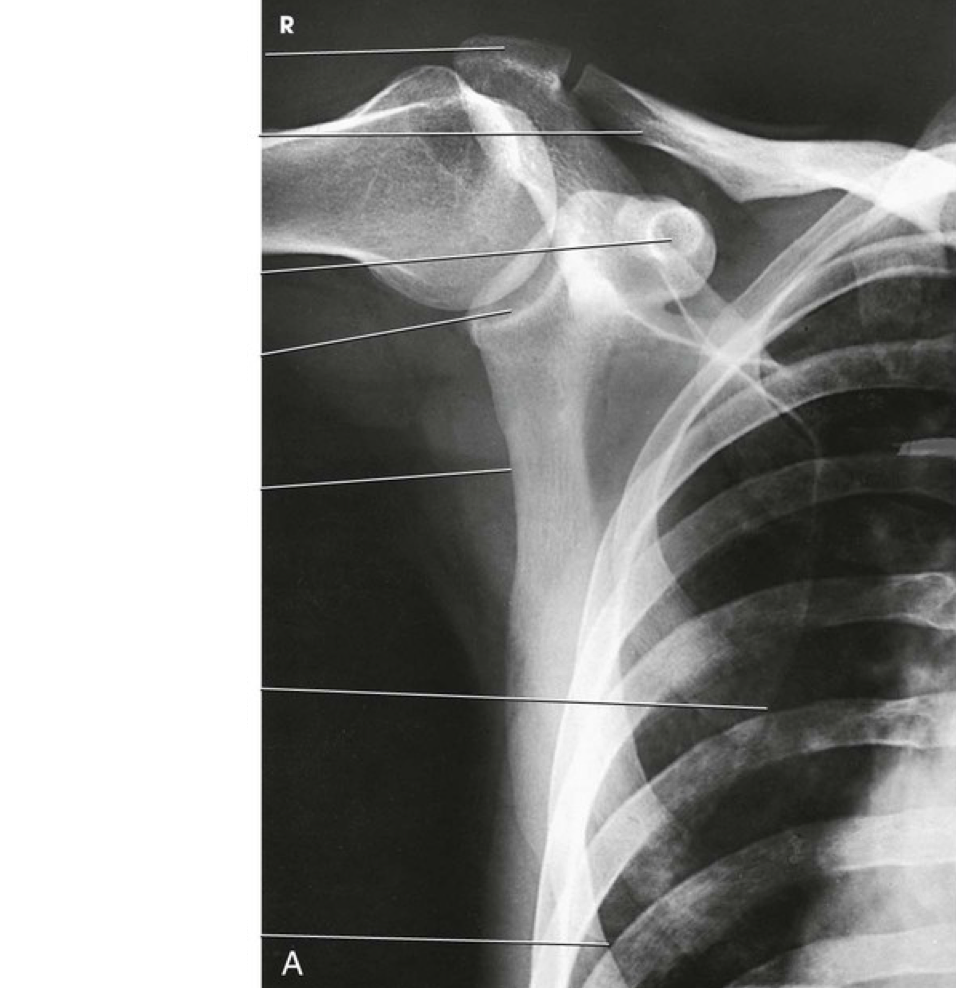

Question 1

Question

Label the image

Image:

3a528096-0507-46cb-a48d-05f40cfb6bb1 (image/png)

Answer

acromion

clavicle

coracoid process

glenoid cavity

lateral border of scapula

medial border of scapula

inferior angle of scapula